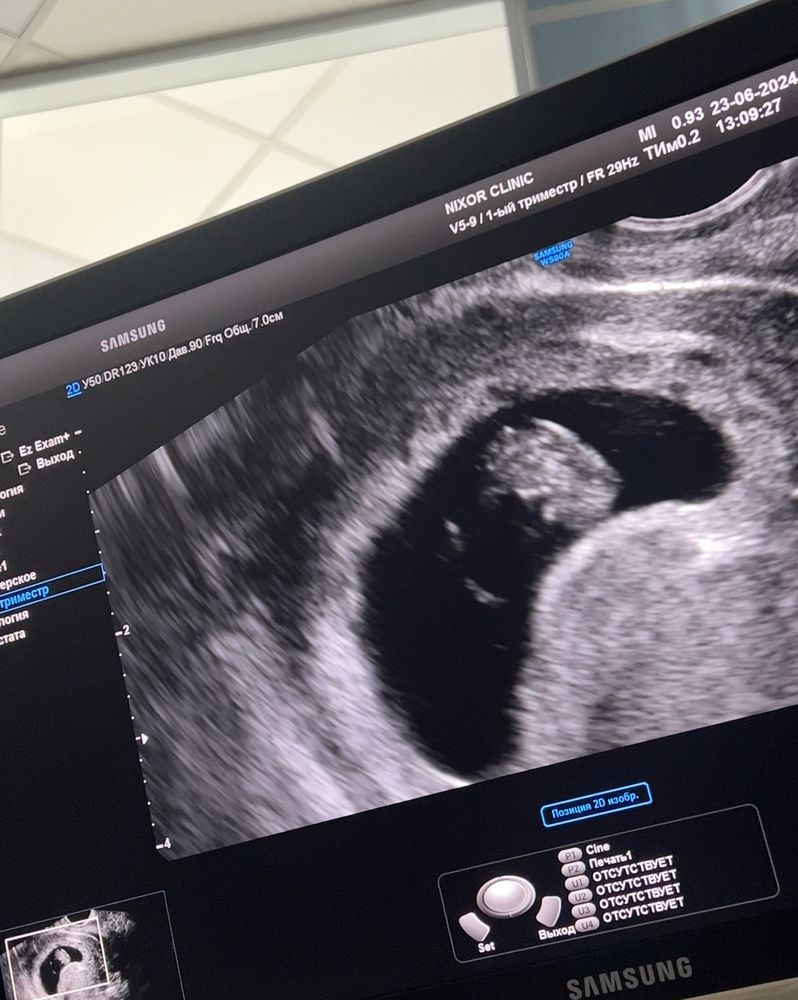

Изображение По узи 9 недель:)